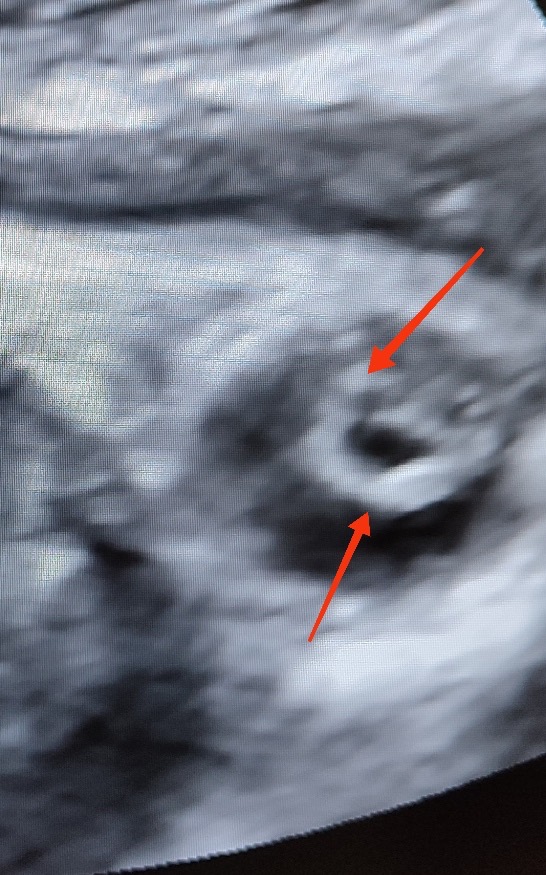

În cazul nostru, ecografia efectuată pe parcursul lunii iunie curent de către medicul imagist Svetlana Basova, la termenul 38 de săptămâni de sarcină a evidențiat la Cristalinul ochiului drept - o creșterea punctiformă a ecogenității în regiunea centrală a cristalinului (cataractă nucleară) iar la Cristalinul ochiului stâng – s-a determinat îngroșarea și creșterea ecogenității inelului periferic, completă (cataractă corticală).